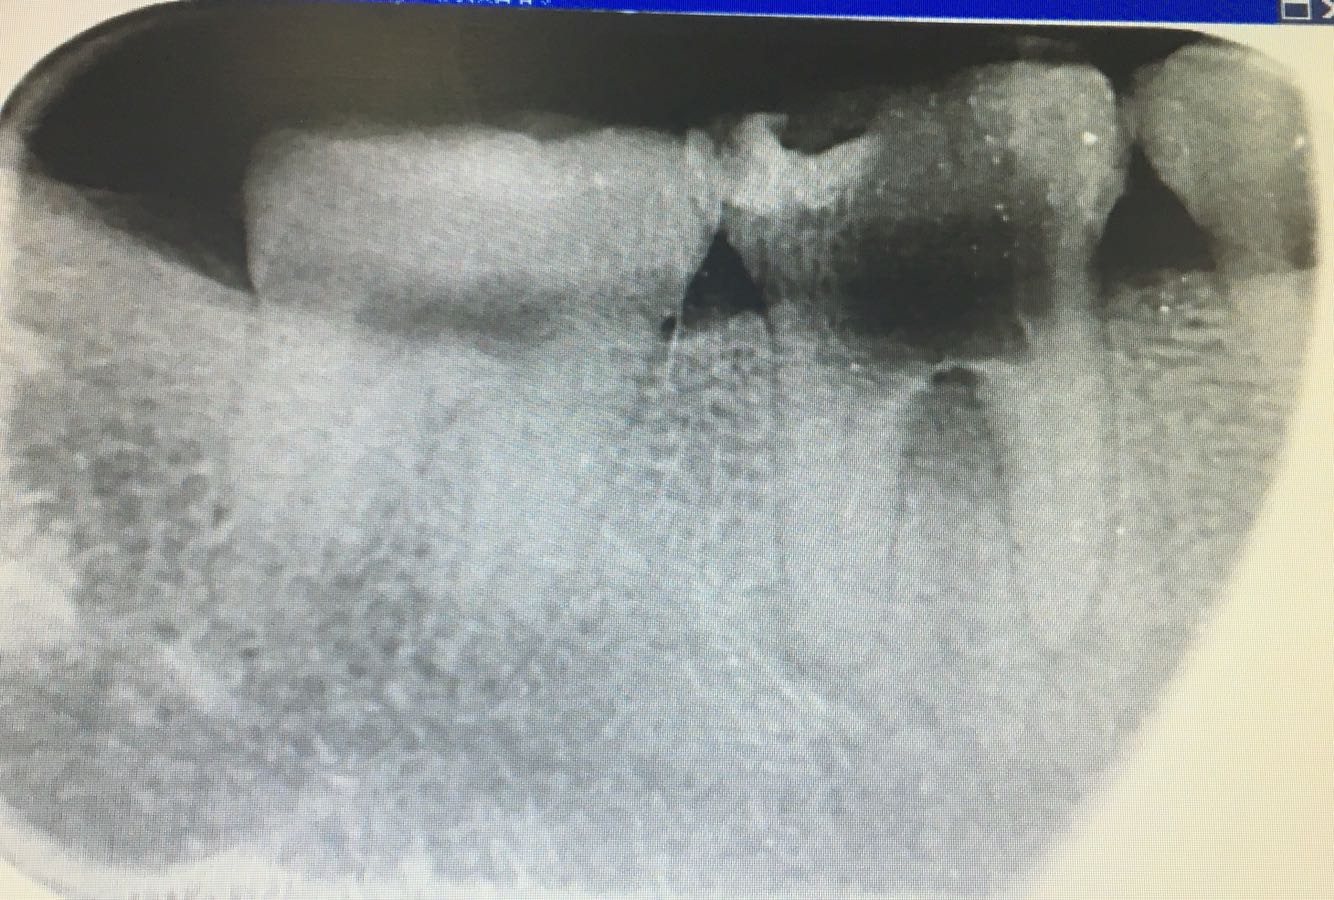

下6大面积龋,不松动,叩痛(一),X线如下,年龄26,大家如何处置

底穿,如图?